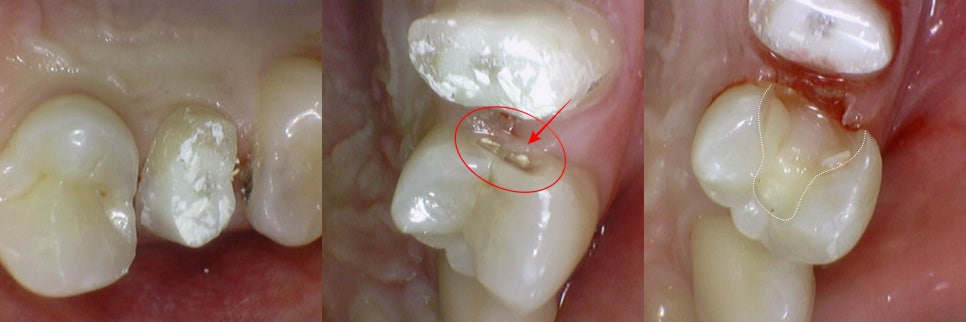

다음으로는, 신경치료를 진행한

치아 앞에 있던 작은 어금니의 인레이 과정입니다.

마찬가지로 충치 제거 후

치아의 뒷면에서 교합면으로 이어지는 형태의

(Distal – Occlusal, DO) 와동을 형성하여

인레이를 올릴 수 있는 모양으로

만드는 것이 필요합니다.

24.12.22 ~ 25.01.13